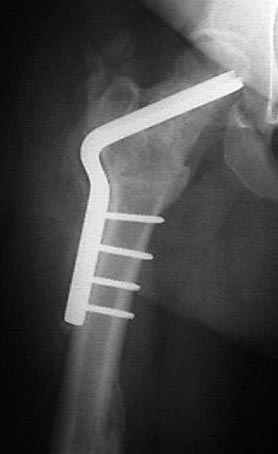

5:24 Рентгенограмма таза, вызывают врача ортопеда (снимок N1), его диагноз: закрытый переломо-вывих правого тазабедренного сустава, получает добро на закрытую репозицию в приемном отделении

7:30 начало операции, больной на спине, попытка репозиции после анестезии N3, укладка больного на боку, доступ Kocher- Langenbeck, состояние седалищнего нерва около 2.5см кровоподтек, через joistick головка бедра приподнята, освобовождение сустава, фрагмент заднего края более 3х4 см репонирован на свое место. После промывания

сустава, репозиция вывиха (N4), фиксация фрагмента 2.7(4) мм шурупами и допольнительно реконструктивной пластиной на 8 дырок, фиксация 3.5мм шурупами проксимально и дистально.

Интраоперционные N5 косая запирательная и N6 подвздошный снимок

11:50 больной в послеоперационной, рентгенограмма N7, компьютерная томограмма в тот же день N8-10

На рисунке N1 предоперационный план лечения ложного сустава шейки бедра- линия ложного сустава, угол и направление введения импланта, клиновидная остеотомия в градусах и миллиметрах, второй снимок после коррекции, расчет, на сколько удлиняется конечность и размеры импланта;

N3 рисунок окончательный снимок, после операции моя рентгенограмма должен выглядеть примерно как эта картина. На N4 снимке клин перед удалением; N5 послеоперации 3 нед.; N6 окончательная рентгенограмма.

варус при проксимальном отделе 95 градусной пластиной.